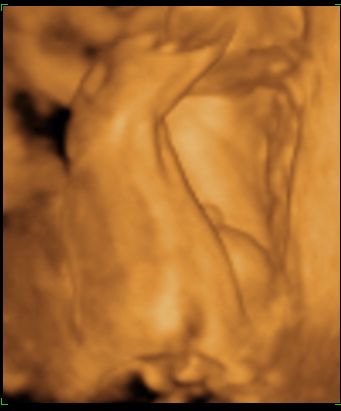

Kisfiú

Kisfiú  Zalán

Zalán

Nyelvnyújtogatás

Nyelvnyújtogatás